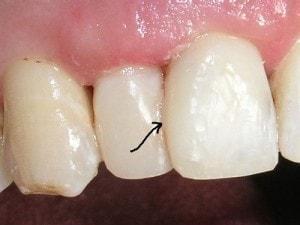

#’s 7 & 8 completed

Arrow shows a distal area which needs to be shaped better. When patient returns I will improve on the contour with a #15 blade.